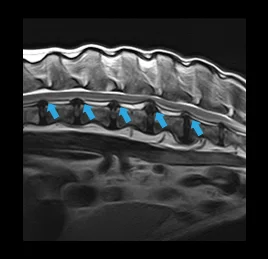

• 척수 질환

디스크 탈출증, 척수염, 허혈성척수병증,

척수공동증, 척수종양, 척추 기형

• 허혈성 척수병증

• 디스크 탈출증